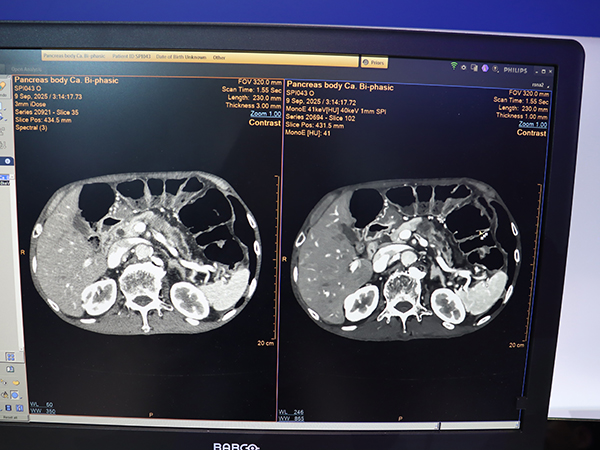

腹部や心臓,頭部など全身領域で使用でき,1mmスライス厚でもノイズの少ない高画質撮影が可能となっている。さらに,仮想単色X線(MonoE)による低エネルギー画像を併用することで,頭部では白質と灰白質のコントラスト向上,腹部では膵がんの境界の明瞭化や血管の視認性向上などが期待できる。AI画像再構成技術はプレミアムCT装置「CT 5300」から継承しており,10年に及ぶ2層検出器CTの集大成として大きくアピールした。

膵がんもSpectral Precise Imageにより明瞭化(左:iDose4・3mm,右:Spectral Precise Image・MonoE 41keV・1mm)